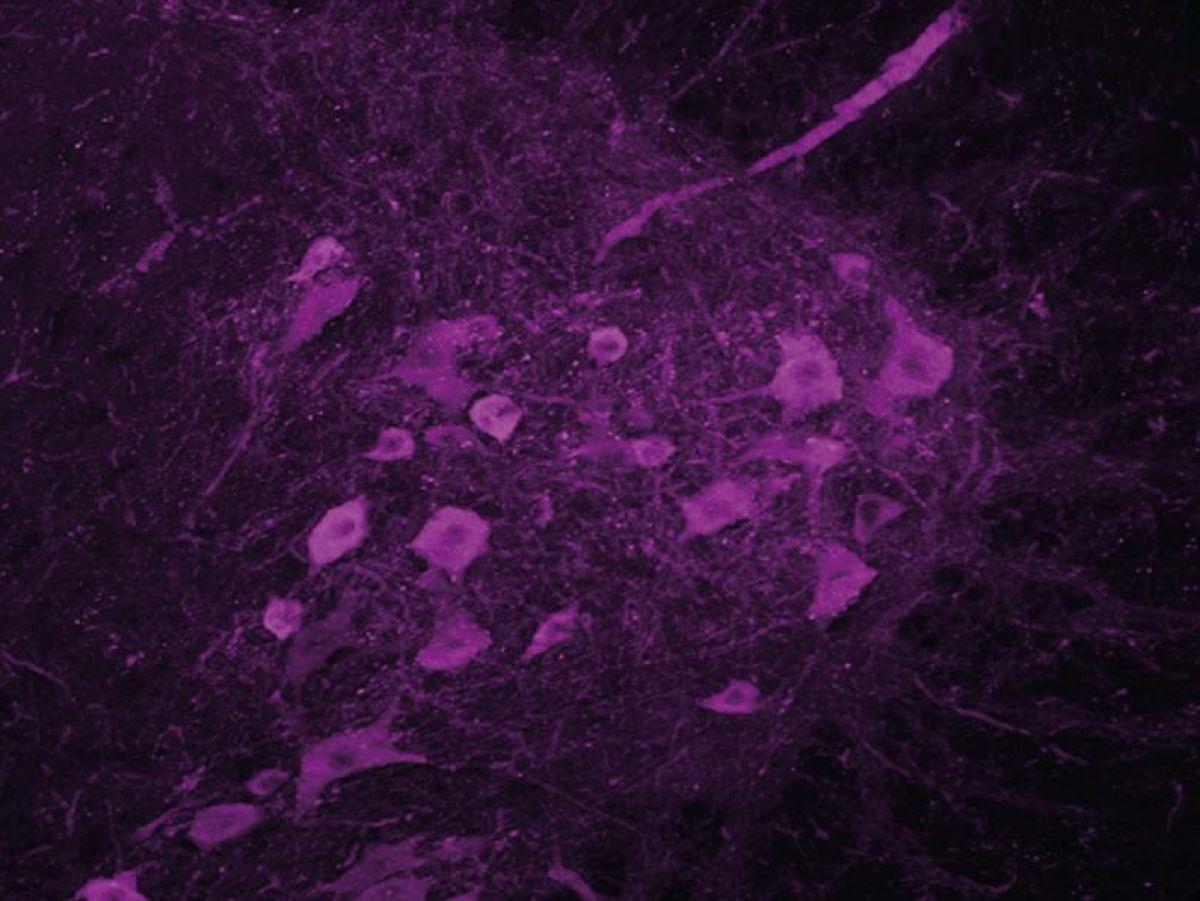

« C’est pour cela que nous nous sommes intéressés à l’hypothalamus, qui est la structure du cerveau en charge de la régulation de notre poids. Nous avons observé que les neurones exprimant l’orexine et la melanin-concentrating hormone (MCH), molécules qui régulent la prise alimentaire mais aussi l’activité et le sommeil, étaient altérés chez les personnes atteintes de SLA, raconte le chercheur. Naturellement, s’il y a des troubles de l’expression de ces neurotransmetteurs dans le cerveau, il y a sûrement aussi des problèmes de sommeil. »

Les souris traitées récupèrent un meilleur sommeil, et leur motoneurone est préservé. »Les motoneurones lombaires semblent ne plus mourir. Ils sont bien là, mais on ne sait pas s’ils sont encore fonctionnels. »